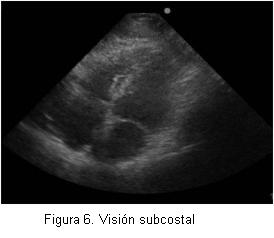

Se ha planteado que el examen ecocardiográfico transtorácico que realiza un anestesiólogo es completamente diferente al examen que realiza el cardiólogo y, por supuesto, no pretende de manera alguna reemplazarlo. Esto se explica porque el anestesiólogo busca resolver preguntas concretas con respecto a lo que ocurre con el corazón en el paciente en su perioperatorio: el estado de la volemia, la contractilidad y tamaño de las cavidades cardíacas. Existen varias publicaciones que avalan la utilidad de la ecocardiografía para los anestesiólogos. Uno de los primeros estudios fue hecho por el grupo de Sloth (6), que evaluaron a pacientes hemodinámicamente inestables en su postoperatorio y obtuvo imágenes satisfactorias por encima del 80% de los casos e imágenes que fueron útiles como guía y manejo de estos pacientes. Durante el preoperatorio se ha planteado la gran utilidad que puede tener la ecocardiografía para evaluar pacientes con presencia de soplos en el examen físico, con capacidad funcional no evaluable y aquellos pacientes con severa alteración de sus capacidades mentales (enfermedad de Alzheimer, deterioro senil) (7). En el intraoperatorio realmente puede ser útil para la monitorización del estado hemodinámico de manera no invasiva (8,9), que permite realizar nuevos diagnósticos, iniciar nuevas terapias y reemplazar otras formas de monitorización, como línea arterial o catéter venoso central. Otra indicación que puede resultar muy interesante es la alta utilidad que puede tener la ecografía durante las maniobras de resucitación cardiopulmonar, ya que en períodos muy breves de detención de las maniobras de masaje cardíaco externo, es posible visualizar a través de la ventana subcostal qué sucede realmente con el miocardio, y es así que se ha demostrado que no siempre el diagnóstico de actividad eléctrica sin pulso corresponde a esta entidad (10).